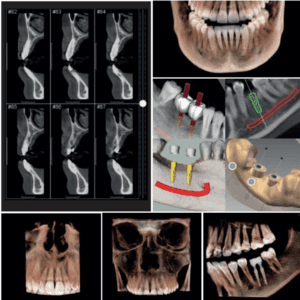

- Equipos de diagnóstico por imágenes

- Equipos de estética y odontología.